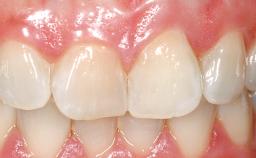

On examination, the patient had a low lip line and only displayed the coronal half of the anterior teeth when smiling.

The crown of tooth 21 was splinted to the adjacent teeth with composite resin, and the gingiva was inflamed.